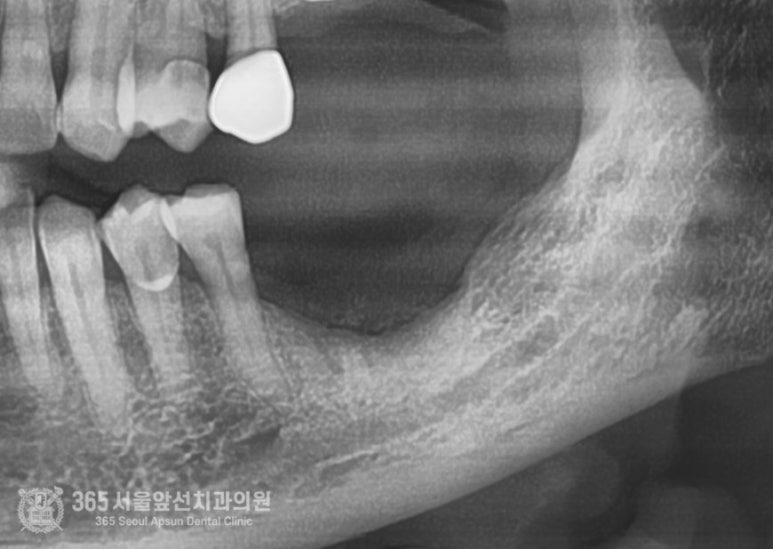

촬영일시: 2024.05.11. 처음 내원 당시 엑스레이 사진입니다. 오래전에 타치과에서 치료 받으셨던 임플란트 부위에 염증이 생겨서 뼈가 거의 남지 않은 상황입니다. 심한 불편감을 호소하셔서 일단 임플란트를 제거하기로 하였습니다.